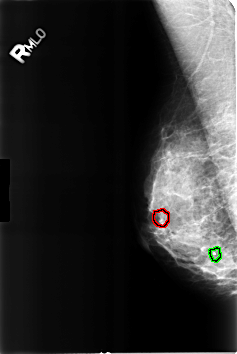

B_3231_1.RIGHT_MLO

FILE: B_3231_1.RIGHT_MLO.OVERLAY

TOTAL_ABNORMALITIES 2

ABNORMALITY 1

LESION_TYPE CALCIFICATION TYPE LUCENT_CENTER DISTRIBUTION N/A

ASSESSMENT 2

SUBTLETY 5

PATHOLOGY BENIGN_WITHOUT_CALLBACK

TOTAL_OUTLINES 1

BOUNDARY

ABNORMALITY 2